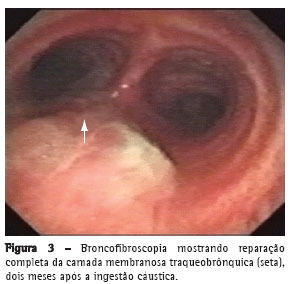

Foi realizada endoscopia digestiva alta, que mostrou a presença de fístula entre o esôfago e brônquio esquerdo, de grandes dimensões, com

passagem do aparelho sem dificuldades (classificação 3b de Zagar(8)). A mucosa esofágica apresentava-se friável com intenso depósito de fibrina. Foi posicionada sonda nasoenteral na segunda porção do duodeno para nutrição (Figura 1).

A radiografia de tórax de controle, após a endoscopia digestiva alta, revelou pneumotórax esquerdo. Foi realizada drenagem torácica esquerda com imediata reexpansão pulmonar. Na broncofibroscopia